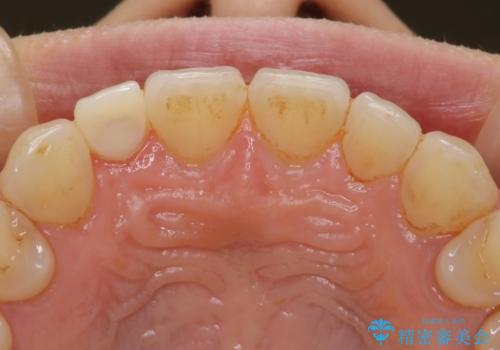

- インビザラインで矯正中の患者様です。リファインメントのタイミングでホームホワイトニングをご希望でしたが、歯の表面にステインがかなり付着していたため、エアフローでのクリーニングからお勧めしました。

歯の表面にステインやバイオフィルムが付着していると、歯面がざらつき更に汚れが付きやすくなるだけでなく、付着物の影響でホワイトニング薬剤の浸透が悪くなりトーンアップ効果が減少します。歯の表面の汚れを落とすことで歯面もツルツルになり、ホワイトニングを行わなくても歯が白くなった様に感じられる場合もあります。